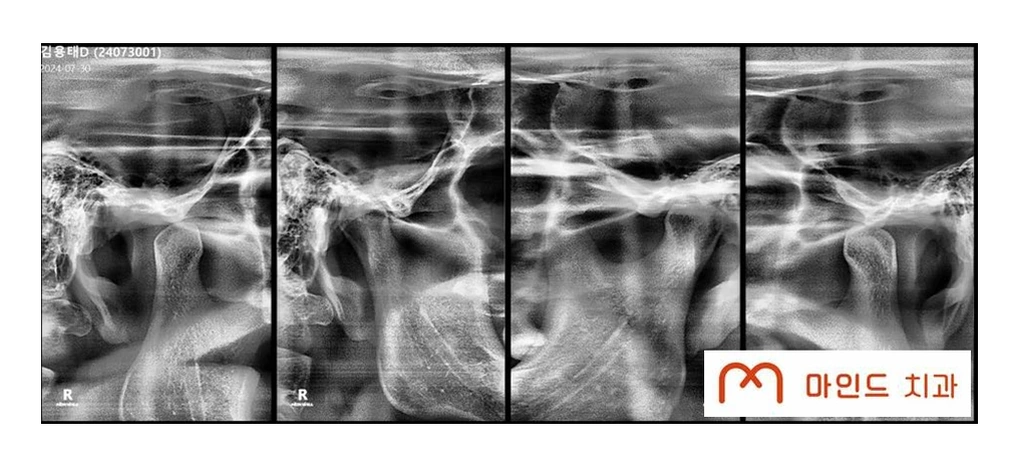

안산치과에서 턱관절 진료를 진행할 때는

구강 상태와 함께

턱관절 움직임, 근육 긴장도, 생활 습관 등을 종합적으로 확인합니다.

필요에 따라

영상 검사와 함께

측두하악장애 분석을 통해

통증의 원인을 보다 세밀하게 파악하게 됩니다.